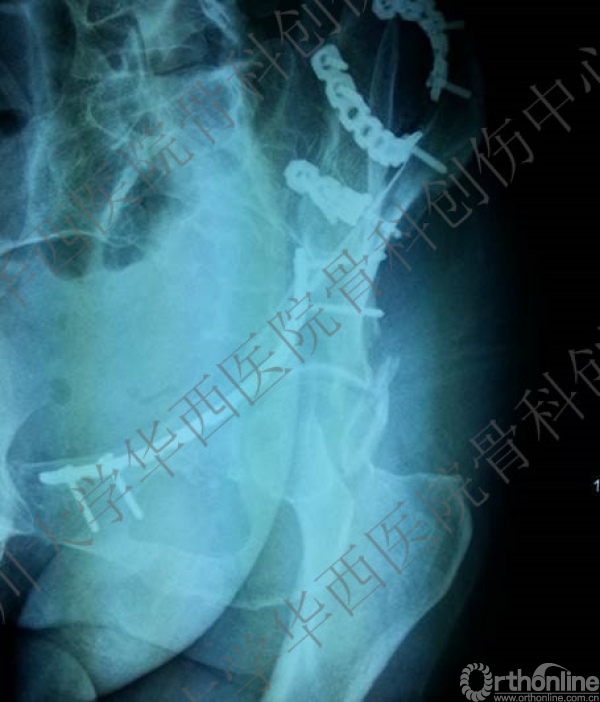

术后三维重建后面观,发现后壁的骨折有明显的移位,后脱位的风险增加,我们决定!

3天后

3天后,行后路切开复位内固定术。

术后CT

术后冠状位及横切面CT扫描,负重区解剖复位

术后CT也证实骨盆形态正常。